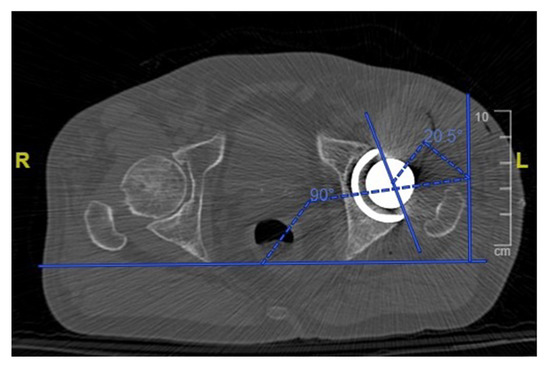

2.2. Postoperative CT Evaluation

| Cup Anteversion | 20.8° (3.43) | 18.3° (7.17) | 0.0930 |

| Cup Anteversion | 4.4° (0–12) | 67% (24) | 92% (33) |